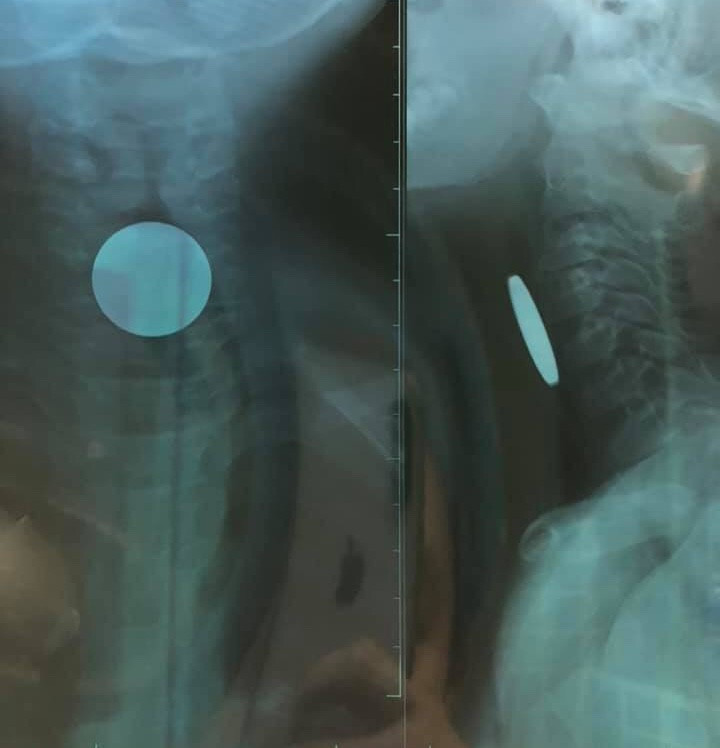

Quảng Bình: Phát hiện đồng xu nằm trong thực quản bé trai 5 tuổi ảnh 1Qua thăm khám các bác sĩ phát hiện một đồng xu nằm trong thực quản cháu P.

Qua thăm khám và chụp X-quang, các bác sỹ phát hiện có dị vật (đồng xu) đoạn thực quản cổ có đường kính 24mm. Sau khi tiến hành nội soi dưới gây mê và gắp đồng xu ra, bệnh nhi P. đã ổn định và có thể xuất viện.

Quảng Bình: Phát hiện đồng xu nằm trong thực quản bé trai 5 tuổi ảnh 2Đồng xu này có đường kính 24 mm.